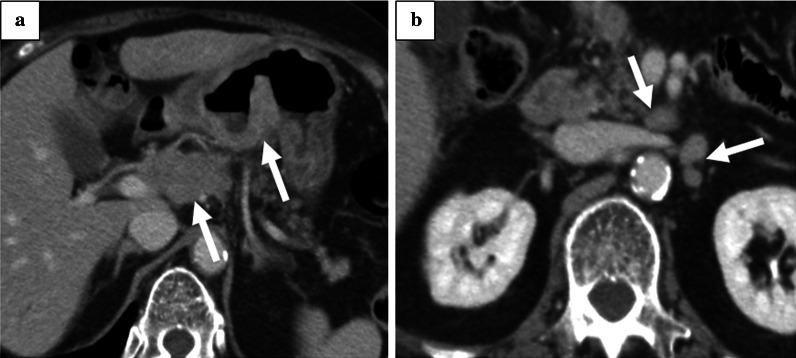

Fig. 2.

Contrast-enhanced CT at the time of diagnosis. a Thicker gastric wall and enlarged regional lymph nodes (No. 8a). b High-density and enlarged No. 16a2 lymph nodes

A 79-year-old woman with hypertension and type 2 diabetes was referred to our hospital for gastric cancer. Gastrointestinal endoscopy revealed a type 3 tumor located in the lower gastric body (Fig. 1). Laboratory tests revealed slight anemia and elevated tumor markers (Table 1). Histopathological examination of a biopsy specimen revealed moderately differentiated tubular carcinoma and weak (1 +) HER2 positivity on immunohistochemical staining. Contrast-enhanced computed tomography (CT) showed a thickened gastric wall and swollen regional (No. 6 and 8a, Fig. 2a) and para-aortic lymph nodes (LNs) (No. 16a2 LNs, Fig. 2b). The patient was diagnosed with advanced gastric cancer (cT4aN2 [No. 3a, 6, 8a] M1 [LYM], stage IV), according to the 8th edition of the Union for International Cancer Control TNM Classification of Malignant Tumors [3].